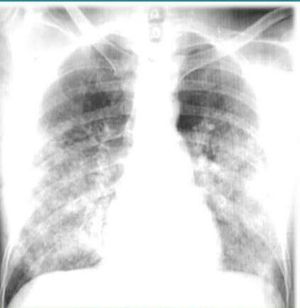

Sir it is pulmonary edema

Hypersenstivity pneumonitis

Aspergillosis

Asbestosis

History would make it specific

Looks like pulmonary edema to me